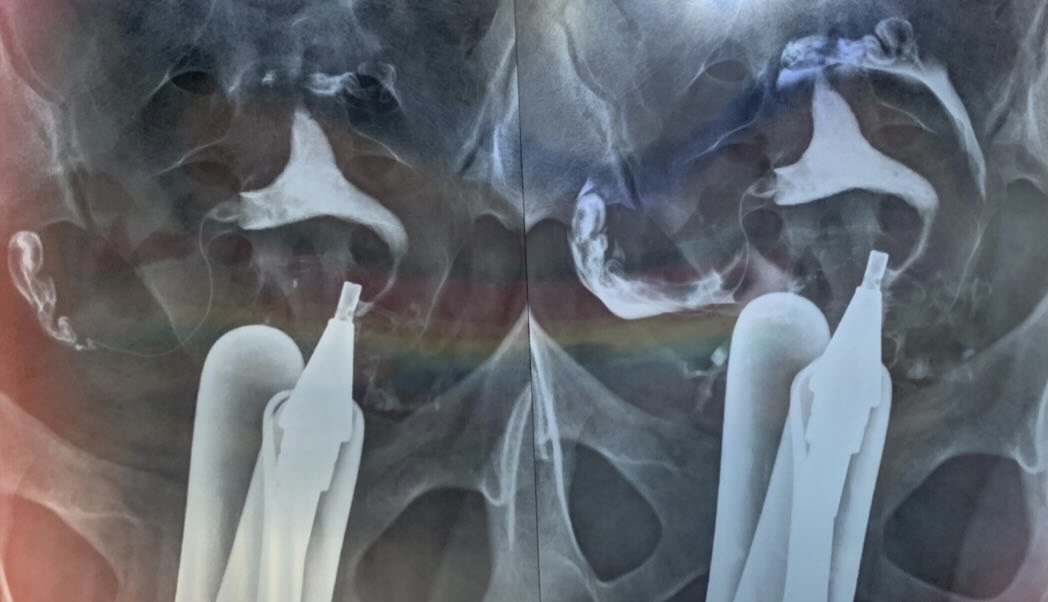

رحم دوشاخ